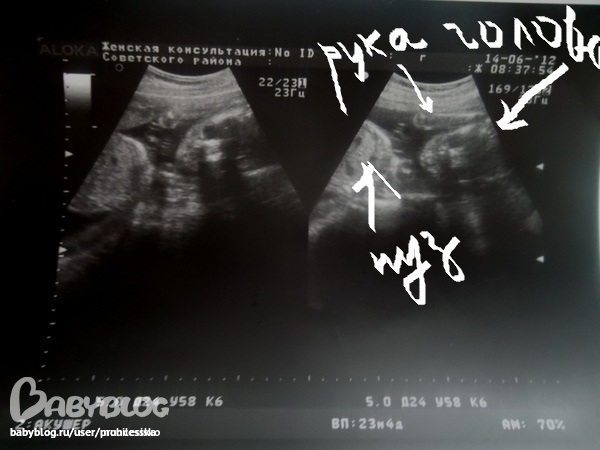

Результаты: УЗИ, КТГ, доплера, скрининга14 числа было второе узи. все хорошо. соответствуем сроку.)) Был шок когда сказали что мальчик.Просто я была всю жизнь у верена что у меня будет дочка. И все вокруг говорили что будет девочка, как то мы даже и не думали что мальчик возможен. Но главное что ребенок хорошо развивается и мы уже настроились на сынишку подбираем ему имя. Дали мне снимок. Принесла домой и не могу понять что где где голова где что??????????? они одинаковые оба или нет??? кто нибудь понял?

Разные. Или один - это увеличенная копия другого. Видно же все отлично :) Справа головка, вон глазки и носик. И ручка, кажется, рядом. А слева тельце начинается. Хорошее фото.

Мне кажется справой стороны голова, там глазки, носик и ротик видно)) он прямо в "камеру "смотрит))